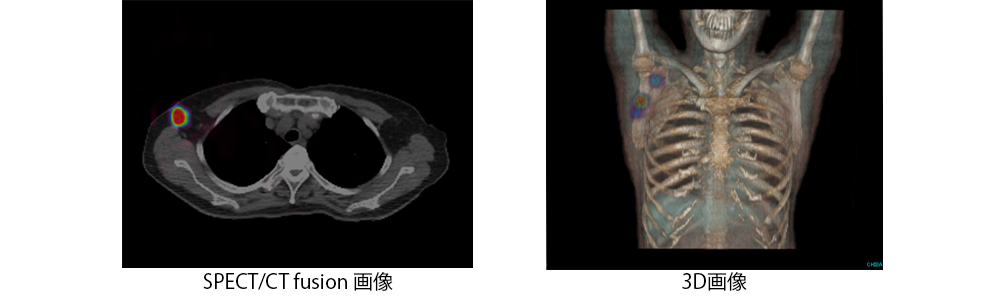

悪性リンパ腫患者のPET像(左),PET横断像(右上),PETとCTの融合像(右下)

PETとCTの融合像を用いることによってより正確な病変の位置情報が得られます。PET-CTにより一度の検査で、この融合画像を取得できます。